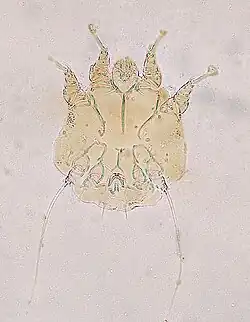

Notoedric mange is caused by the sarcoptic mite Notoedres cati that belongs to the family Sarcoptidae that consists of the burrowing mites. N. cati burrows its way through the skin of the host animal, which results in intense itching. Characteristic symptoms for Notoedric mange result from an allergic reaction of the host's body against the mites' extracellular products and also of the mechanical damage resulting from burrowing through skin.[11][12]

Most commonly N. cati as a cause of Notoedric mange may be diagnosed from a skin scraping sample with a direct microscopic identification of the mite, because there are a large number of mites present on the skin. Characteristic and systemic symptoms of Notoedric mange also help with diagnosis.[12]